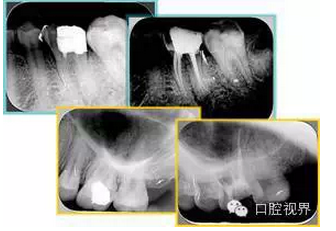

如圖為塑化加根充處理后牙齒 X 線片。